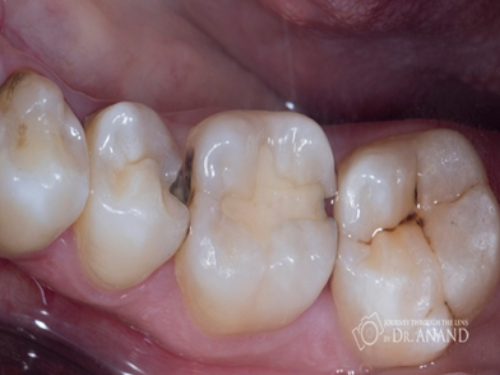

Caries prone areas

Some tooth surfaces have more chances of caries due to their anatomy food lodgment is inevitable. Most caries susceptible areas are;

Steps in composite restoration

It is mostly completed in single sitting. Tooth appeared to be carious is prepared to receive composite. This procedure needs to be done in proper isolation to have good tooth to composite bond. After completion of the restoration, it is polished to get smooth and glossy surface so that there is no food retention.